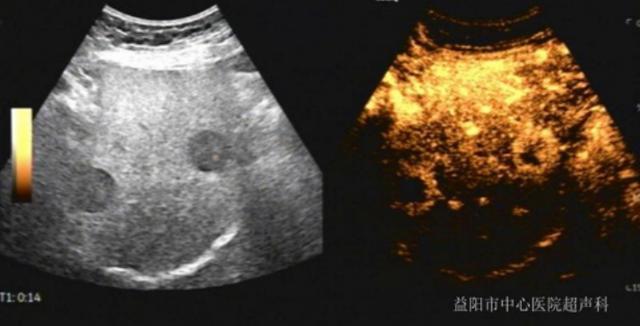

肝脏超声造影,专业上称为对比增强超声(CEUS),是在常规超声检查的基础上,通过静脉注射一种安全的造影剂,实时、动态地观察肝脏及其病变内部血流灌注情况的高级影像学技术。它让医生能直观地“看”到结节的血流如何进入、分布和退出,这是鉴别其性质的核心依据。

不同性质的结节,其血流模式如同独特的“指纹”。2019年及2024年版《原发性肝癌诊疗规范》均已将CEUS列为诊断肝细胞癌的四大增强影像方法之一,凸显了其权威地位。